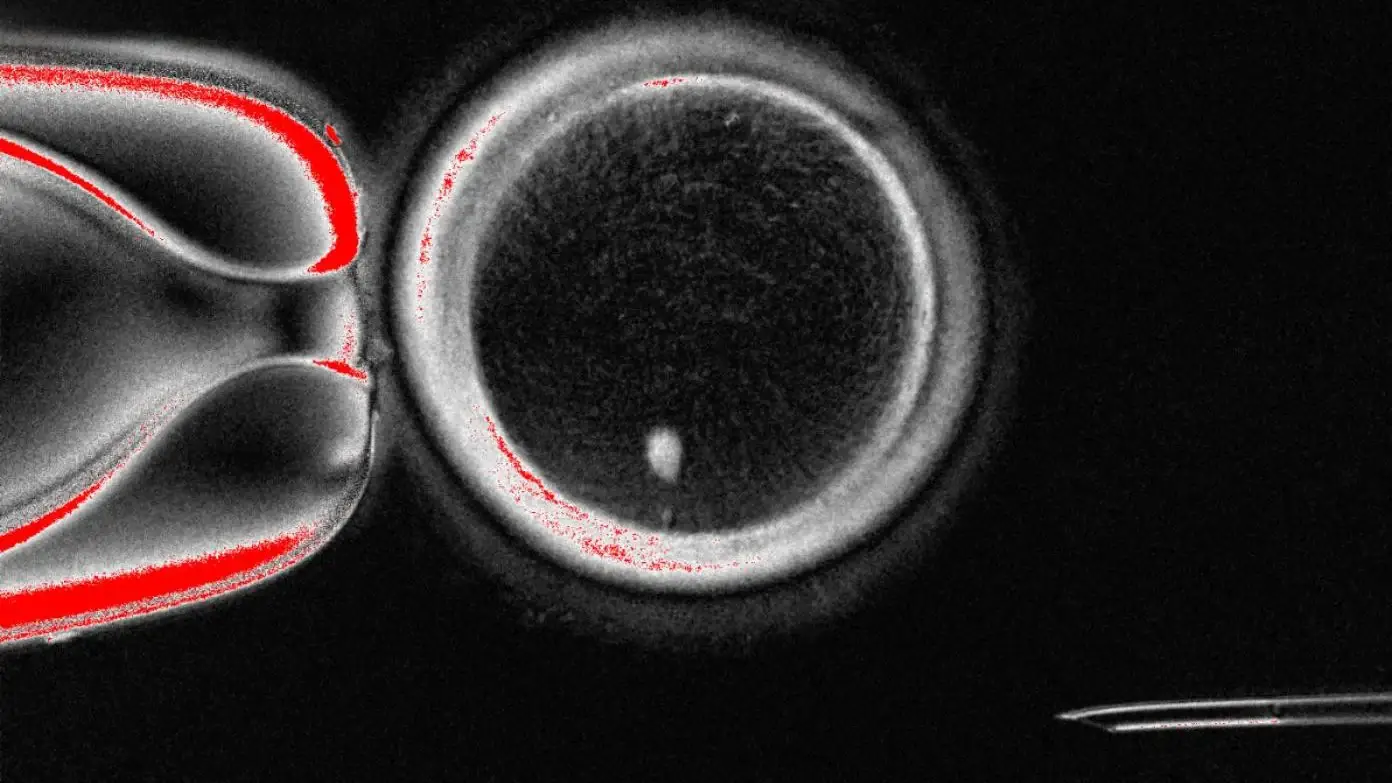

In short, American researchers demonstrated it was possible to replace the DNA from an egg with the genetic material from another person’s skin cells, and turn it into a sex cell ready for fertilisation.

The process involves taking the nucleus, which is the control centre of the cell which stores its genetic material, from a patient’s own skin cells.

These are then implanted into a donor egg with its nucleus removed in a process known as somatic cell nuclear transfer.

To combat this, researchers in the US removed the nucleus from skin cells and implanted it in a donor egg.

To remove the extra chromosomes, they carried out a process they have called mitomeiosis.

This mimics natural cell division that causes one set of chromosomes to be discarded, leaving behind a healthy reproductive cell capable of being fertilised.

The team was able to create 82 functional developing eggs known as oocytes, which were fertilised using sperm in a lab.

Almost one in 10 (nine percent) of the fertilised eggs went on to develop to the blastocyst stage, which is when cells rapidly divide around six days after fertilisation.